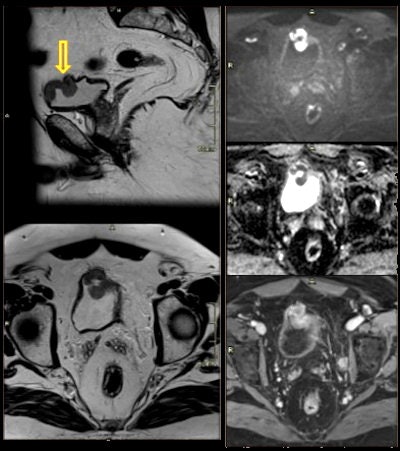

In their analysis, they identified the following genitourinary incidental findings:

- Rectal lesions: focal wall thickening due to primary neoplasms or metastasic disease

- Rectal or perianal fistula: narrow cavity or channel stretching between the bowel and the skin

- Presacral fibrosis: Presacral soft tissue is found in up to half of patients after treatment for rectal cancer.